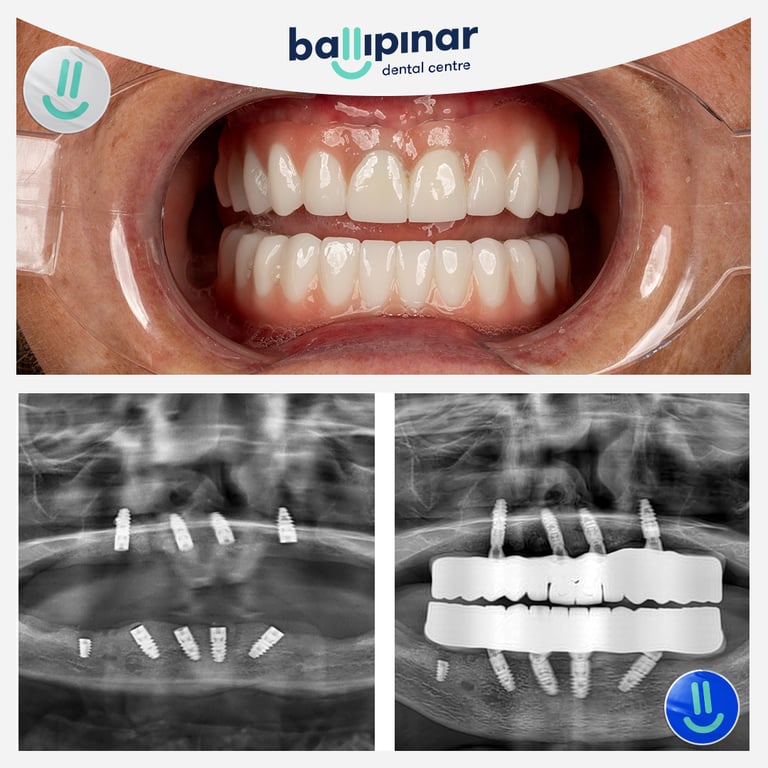

Dental implants Before & After

Explore all the before and after photos of dental implant procedures performed by Ballipinar in Turkey. Contact us today to achieve a beautiful smile.